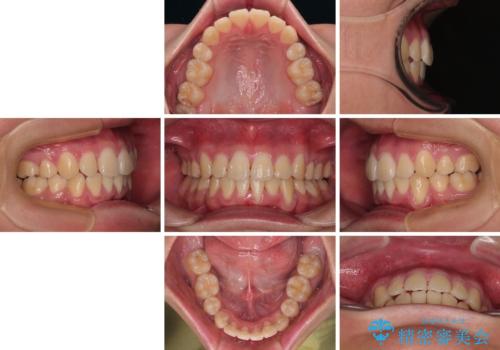

移動が順調に進み、1年半の短期間で治療を終えることができました。

前方に突出した上顎前歯の傾斜も改善されました。

特に前歯のデコボコが顕著であり、上下左右第一小臼歯の4本を抜歯し、ワイヤー装置を使用して咬み合わせ高さを改善しながら、歯列を整えて行くこととしました。